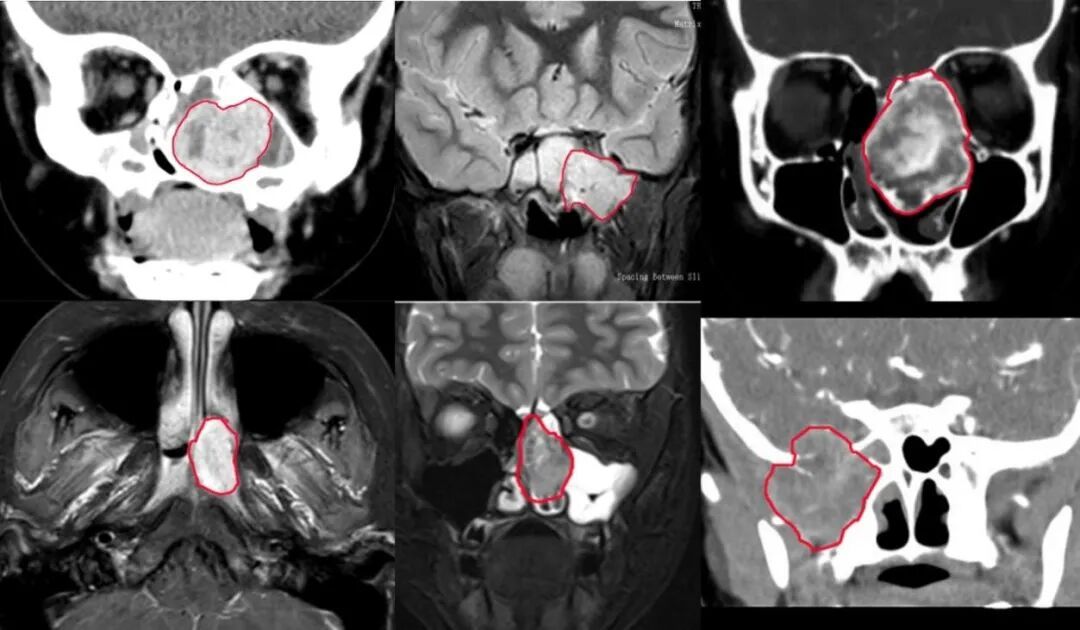

小航,9岁男孩,因“右鼻塞3个月,右面部渐进性膨隆”来诊。起初以为是鼻炎,当地医院治疗了两个月,没有改善。鼻内镜检查发现右侧鼻腔巨大灰红色肿物,增强MRI显示是一个血供丰富的肿瘤,已侵犯翼腭窝、颞下窝、眼眶及颅底,压迫视神经和颈内动脉。需要手术切除,但是手术风险大,出血多,我们立即启动MDT:影像科:完成高分辨率增强CT/MRI,构建导航模型;眼科:评估眼球运动的情况和视力;神经外科:评估肿瘤对颅内的影响;心内科:血管介入,术前栓塞肿瘤主要供血动脉;耳鼻喉科:在电磁导航辅助下,通过鼻内镜切除肿瘤,并修复颅底缺损。手术非常成功,小航的肿瘤被完整切除,面部恢复正常且无任何疤痕。

图 1 小航肿瘤范围示意图